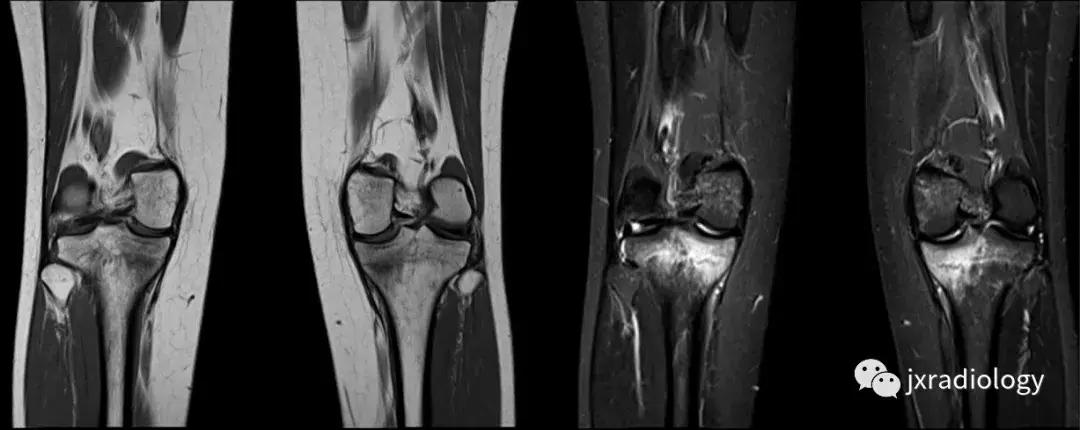

图3:应力(疲劳)骨折:女,25岁,最近在没有适当热身的情况下在健身房参与剧烈运动的冠状位T1WI和STIR图像。她主诉出现双侧内侧胫骨疼痛。在双侧胫骨中,内侧近端应力性骨折是明显的。

图4:SIF(软骨下不全性骨折):在过去,每当在股骨内侧髁上视察到这种软骨下病变时,它就被标记为膝关节自发性骨坏死(SONK)。现在它被认为是一个不全性骨折。这些不全性骨折通常发生在股骨内侧髁和股骨头,并存在于老年人中(它们与骨质疏松症和生物力学改变相关,如在不稳定的半月板损伤中。与其他应力性骨折类似,低信号的骨折线在水敏性序列(a,b:冠状和矢状PDWI-FS)上被高信号的骨髓水肿包围。

图5:长期的SIF(软骨下不全性骨折)伴股骨外侧髁软骨下塌陷、大面积水肿(不如上图中显示的内侧髁位置常见)。

图6:内侧胫骨平台上不常见的SIF(软骨下不全性骨折)(a,b:矢状和冠状PDWI-FS)。